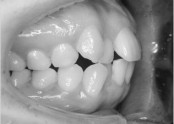

• 치아교정 덧니 교정

• 36